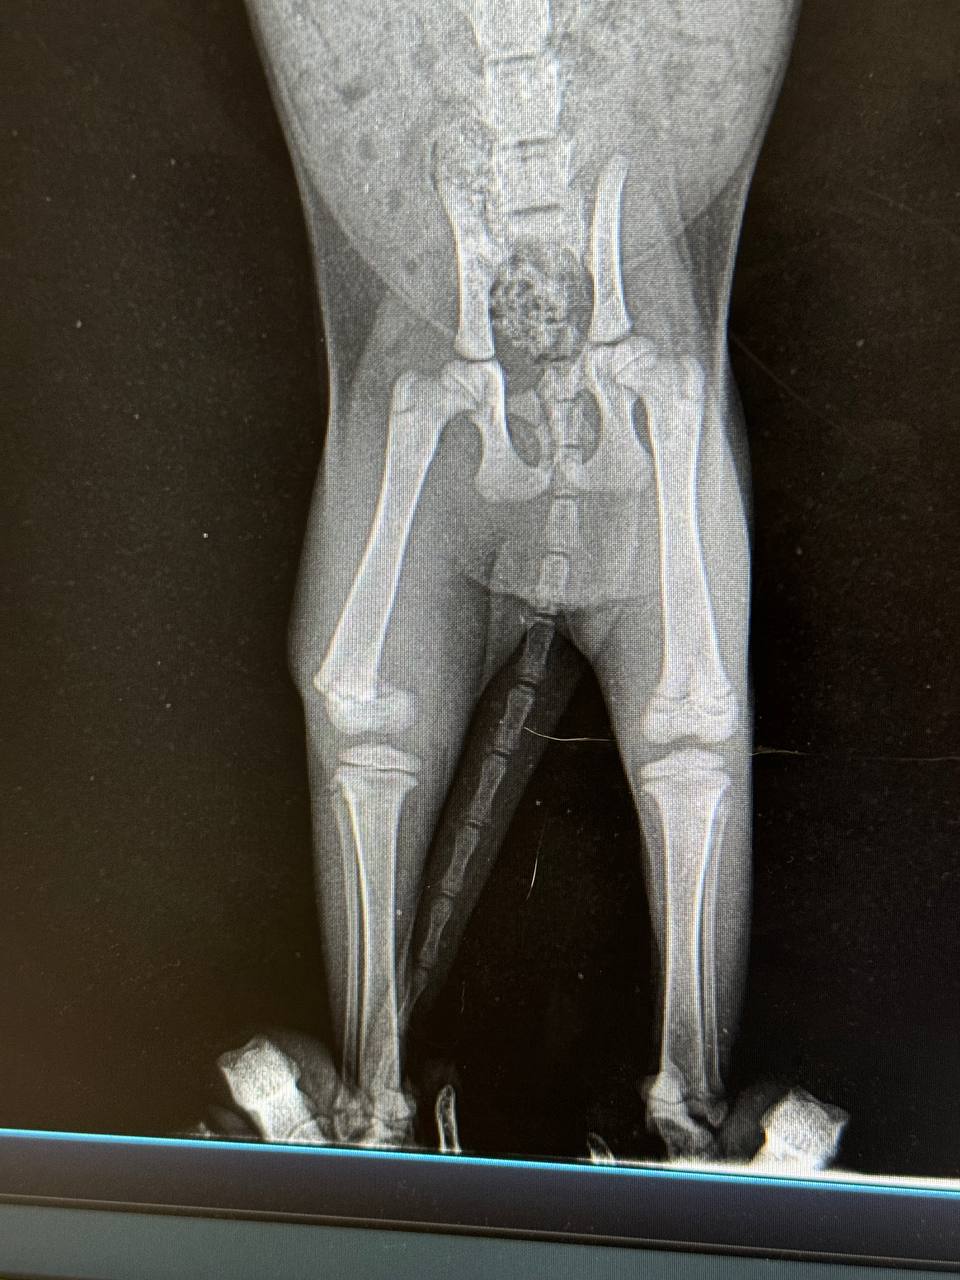

В клинике сделали рентген - это перелом лапки, естественно если сейчас не заняться здоровьем малышки, она просто не выживет…

Просто реставрация коленной чашки это кропотливо. Она у малыша просто срезана((

По красоте( срезана чашечка,резекция естественным путём (тут имплант ставить. Только убедитесь что не будут класть гипс,а Маринос такие вещи любит отрезать если честно

И не вижу подвздошной кости,пс - вижу) нет перегородки между правой и левой подвздошкой